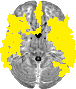

| Left Frontal Pole | 14 | 27% | 1881 |

| Left Insular Cortex | 15 | 60% | 692 |

| Left Superior Frontal Gyrus | 16 | 13% | 338 |

| Left Middle Frontal Gyrus | 17 | 12% | 316 |

| Left Inferior Frontal Gyrus, pars triangularis | 18 | 3% | 17 |

| Left Inferior Frontal Gyrus, pars opercularis | 19 | 24% | 178 |

| Left Precentral Gyrus | 20 | 19% | 815 |

| Left Temporal Pole | 21 | 52% | 1219 |

| Left Superior Temporal Gyrus, anterior division | 22 | 54% | 136 |

| Left Superior Temporal Gyrus, posterior division | 23 | 56% | 490 |

| Left Middle Temporal Gyrus, anterior division | 24 | 50% | 222 |

| Left Middle Temporal Gyrus, posterior division | 25 | 61% | 775 |

| Left Middle Temporal Gyrus, temporooccipital part | 26 | 23% | 196 |

| Left Inferior Temporal Gyrus, posterior division | 28 | 34% | 335 |

| Left Inferior Temporal Gyrus, temporooccipital part | 29 | 21% | 149 |

| Left Postcentral Gyrus | 30 | 16% | 598 |

| Left Supramarginal Gyrus, anterior division | 32 | 32% | 306 |

| Left Supramarginal Gyrus, posterior division | 33 | 35% | 369 |

| Left Angular Gyrus | 34 | 43% | 409 |

| Left Lateral Occipital Cortex, superior division | 35 | 15% | 744 |

| Left Lateral Occipital Cortex, inferior division | 36 | 20% | 405 |

| Left Intracalcarine Cortex | 37 | 3% | 20 |

| Left Frontal Medial Cortex | 38 | 35% | 149 |

| Left Juxtapositional Lobule Cortex | 39 | 22% | 137 |

| Left Subcallosal Cortex | 40 | 14% | 71 |

| Left Paracingulate Gyrus | 41 | 54% | 724 |

| Left Cingulate Gyrus, anterior division | 42 | 27% | 272 |

| Left Cingulate Gyrus, posterior division | 43 | 15% | 148 |

| Left Precuneous Cortex | 44 | 4% | 92 |

| Left Frontal Orbital Cortex | 46 | 47% | 804 |

| Left Parahippocampal Gyrus, anterior division | 47 | 28% | 154 |

| Left Lingual Gyrus | 49 | 14% | 214 |

| Left Temporal Fusiform Cortex, anterior division | 50 | 18% | 57 |

| Left Temporal Fusiform Cortex, posterior division | 51 | 19% | 161 |

| Left Temporal Occipital Fusiform Cortex | 52 | 3% | 17 |

| Left Occipital Fusiform Gyrus | 53 | 22% | 197 |

| Left Frontal Operculum Cortex | 54 | 34% | 124 |

| Left Central Opercular Cortex | 55 | 55% | 542 |

| Left Parietal Operculum Cortex | 56 | 27% | 153 |

| Left Planum Polare | 57 | 56% | 202 |

| Left Heschl's Gyrus (includes H1 and H2) | 58 | 49% | 158 |

| Left Planum Temporale | 59 | 27% | 142 |

| Left Supracalcarine Cortex | 60 | 3% | 2 |

| Left Occipital Pole | 61 | 35% | 925 |

| Right Frontal Pole | 62 | 30% | 2494 |

| Right Insular Cortex | 63 | 51% | 602 |

| Right Superior Frontal Gyrus | 64 | 5% | 132 |

| Right Middle Frontal Gyrus | 65 | 29% | 752 |

| Right Inferior Frontal Gyrus, pars triangularis | 66 | 21% | 102 |

| Right Inferior Frontal Gyrus, pars opercularis | 67 | 40% | 262 |

| Right Precentral Gyrus | 68 | 6% | 243 |

| Right Temporal Pole | 69 | 43% | 1018 |

| Right Superior Temporal Gyrus, anterior division | 70 | 41% | 111 |

| Right Superior Temporal Gyrus, posterior division | 71 | 42% | 396 |

| Right Middle Temporal Gyrus, anterior division | 72 | 48% | 191 |

| Right Middle Temporal Gyrus, posterior division | 73 | 39% | 491 |

| Right Middle Temporal Gyrus, temporooccipital part | 74 | 37% | 428 |

| Right Inferior Temporal Gyrus, anterior division | 75 | 11% | 36 |

| Right Inferior Temporal Gyrus, posterior division | 76 | 20% | 193 |

| Right Inferior Temporal Gyrus, temporooccipital part | 77 | 19% | 148 |

| Right Postcentral Gyrus | 78 | 0% | 7 |

| Right Superior Parietal Lobule | 79 | 12% | 174 |

| Right Supramarginal Gyrus, anterior division | 80 | 3% | 27 |

| Right Supramarginal Gyrus, posterior division | 81 | 24% | 296 |

| Right Angular Gyrus | 82 | 43% | 628 |

| Right Lateral Occipital Cortex, superior division | 83 | 9% | 441 |

| Right Lateral Occipital Cortex, inferior division | 84 | 16% | 325 |

| Right Intracalcarine Cortex | 85 | 11% | 83 |

| Right Frontal Medial Cortex | 86 | 39% | 175 |

| Right Juxtapositional Lobule Cortex | 87 | 14% | 104 |

| Right Subcallosal Cortex | 88 | 36% | 176 |

| Right Paracingulate Gyrus | 89 | 59% | 812 |

| Right Cingulate Gyrus, anterior division | 90 | 43% | 544 |

| Right Cingulate Gyrus, posterior division | 91 | 15% | 174 |

| Right Precuneous Cortex | 92 | 2% | 51 |

| Right Frontal Orbital Cortex | 94 | 45% | 655 |

| Right Parahippocampal Gyrus, anterior division | 95 | 12% | 77 |

| Right Lingual Gyrus | 97 | 5% | 83 |

| Right Temporal Fusiform Cortex, anterior division | 98 | 15% | 45 |

| Right Temporal Fusiform Cortex, posterior division | 99 | 23% | 162 |

| Right Temporal Occipital Fusiform Cortex | 100 | 12% | 99 |

| Right Occipital Fusiform Gyrus | 101 | 27% | 237 |

| Right Frontal Operculum Cortex | 102 | 45% | 147 |

| Right Central Opercular Cortex | 103 | 48% | 434 |

| Right Parietal Operculum Cortex | 104 | 38% | 204 |

| Right Planum Polare | 105 | 56% | 217 |

| Right Heschl's Gyrus (includes H1 and H2) | 106 | 71% | 201 |

| Right Planum Temporale | 107 | 54% | 224 |

| Right Supracalcarine Cortex | 108 | 10% | 14 |

| Right Occipital Pole | 109 | 34% | 856 |